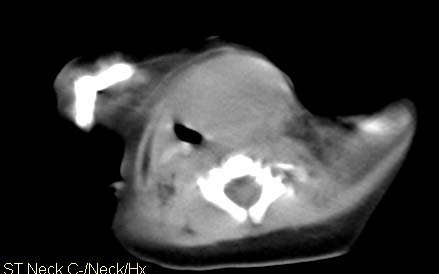

男,26天,发现左侧颈部包块5天,质较硬,患儿不哭不吵,无明显发热,头向右侧歪斜,其父母诉患儿出生时正常,昨天查血象wbc19.4×10的9次方/l,b超考虑来源于甲状腺的恶性肿瘤,我科认为肿块内有低密度区,而且病程发展较快,血象高,考虑炎性病变可能大。患儿年龄太小没做增强。请大家提出高见。

男,26天,发现左侧颈部包块5天,质较硬,患儿不哭不吵,无明显发热,头向右侧歪斜,其父母诉患儿出生时正常,昨天查血象wbc19.4×10的9次方/l,b超考虑来源于甲状腺的恶性肿瘤,我科认为肿块内有低密度区,而且病程发展较快,应该首先排除血肿,其次考虑感染

随访结果:炎症(患儿经过一星期抗炎治疗后颈部包块明显缩小,现已经正常)。